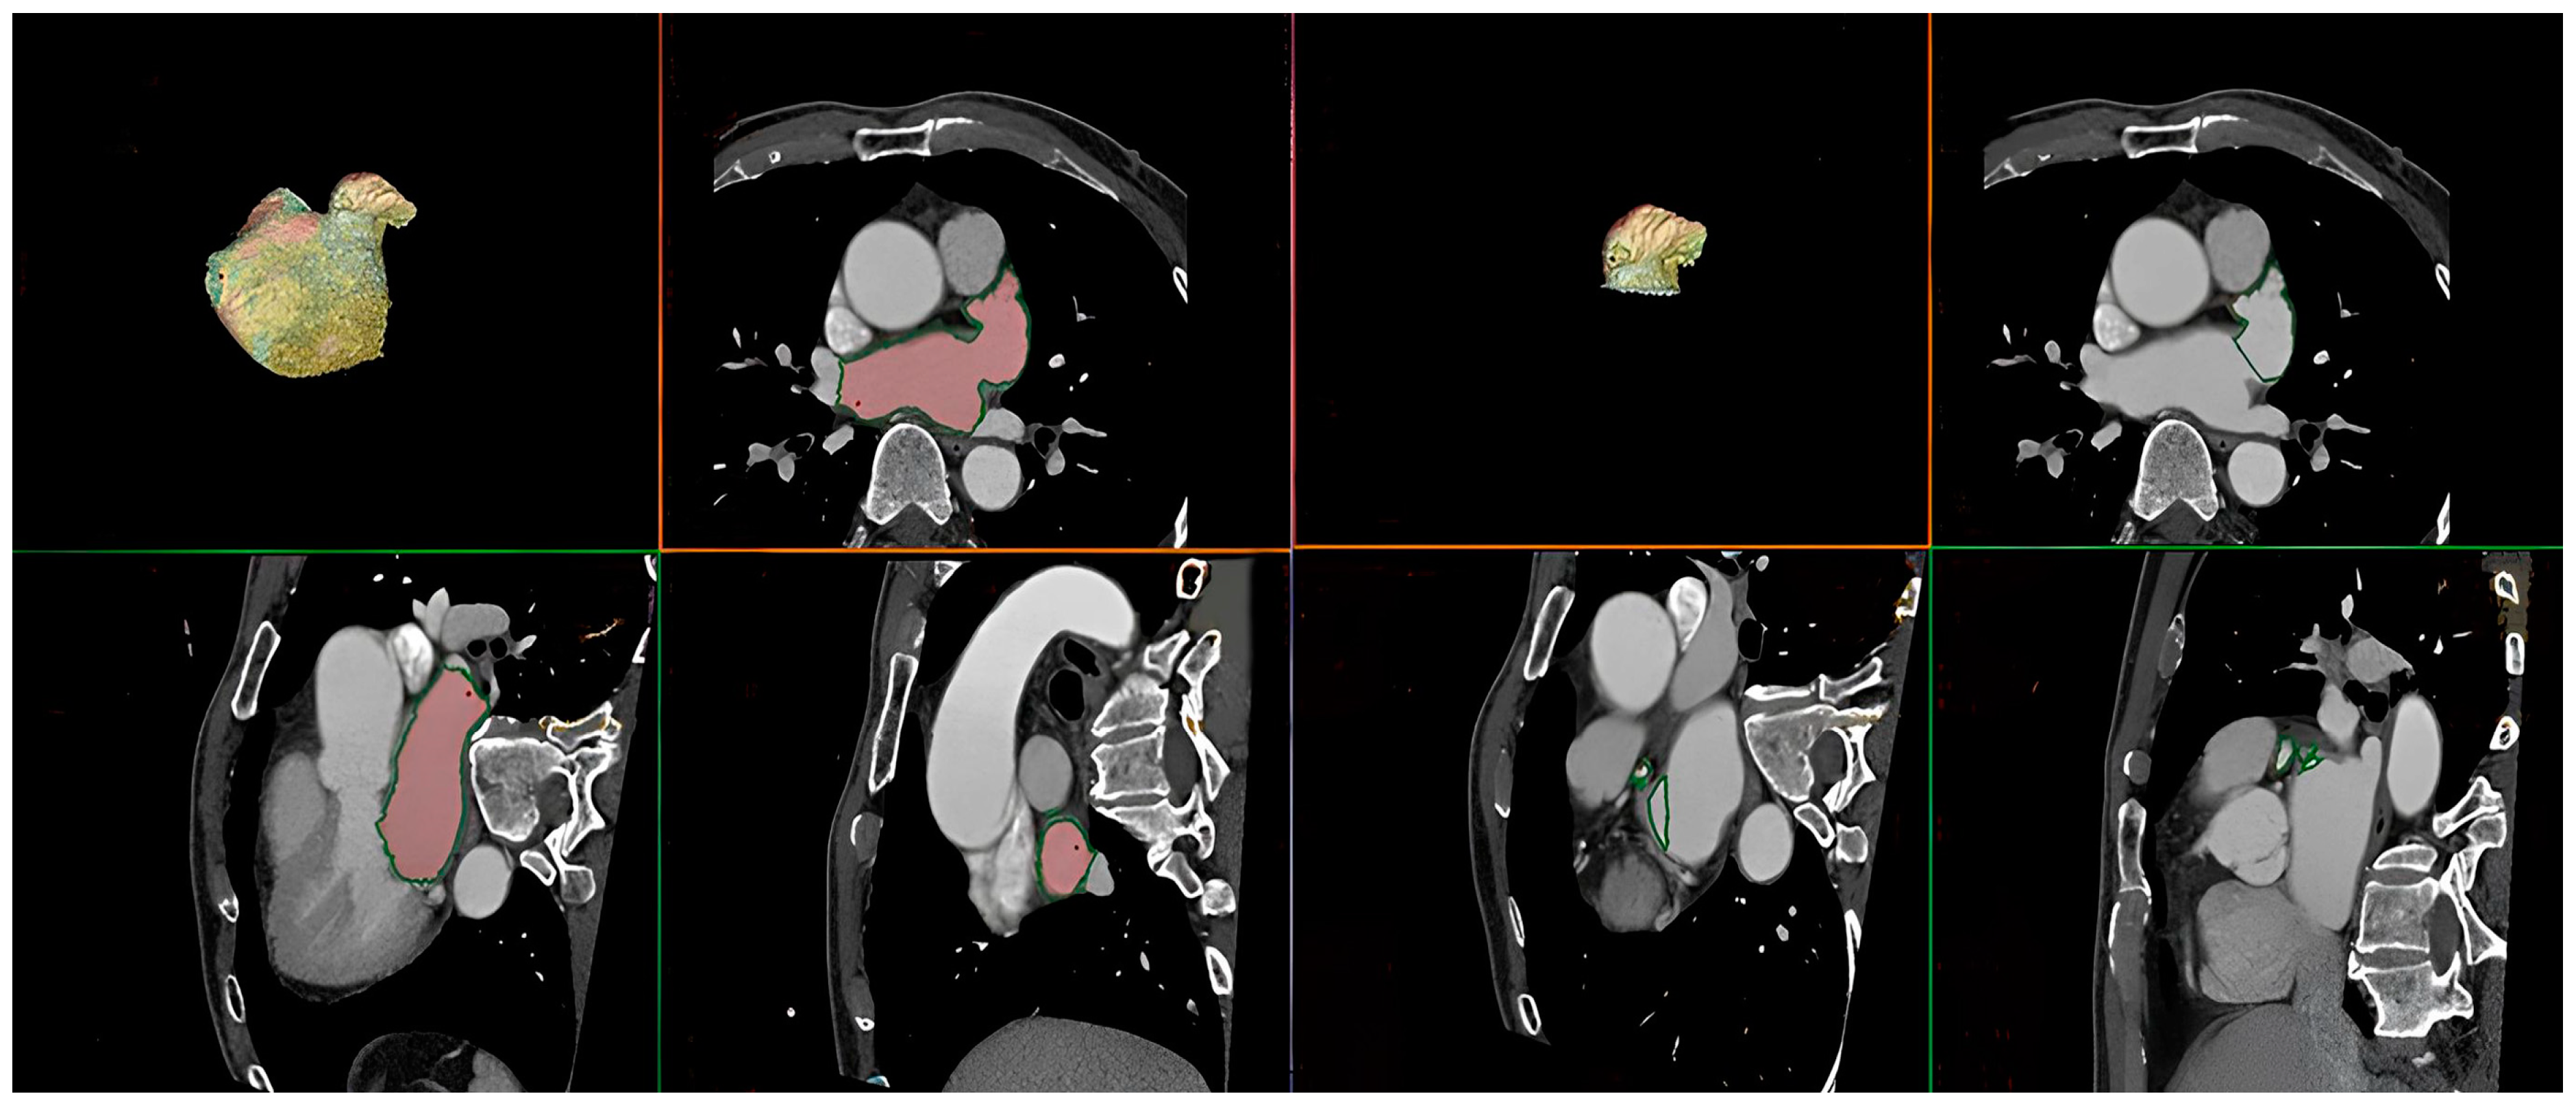

2.2. Multislice Computed Tomography